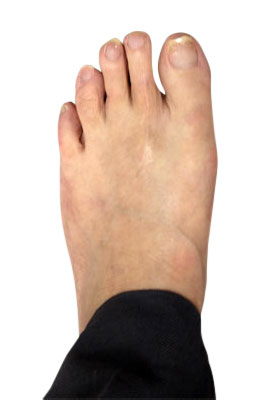

Before

Lapidus Forever Bunionectomy™ Before image

After

Lapidus Forever Bunionectomy™ after image

Lapidus Forever Bunionectomy™

Whitney, a 47-year-old businesswoman who could not fit into her dress shoes because of her bunion and terrible calluses caused by it. We performed a Lapidus Forever Bunionectomy™ on her big toes and she was able to bear weight on her foot 2 weeks after surgery and was back in her heels at 8 weeks post-surgery with no pain and now an amazing looking foot. After image was taken 12 weeks post-op.